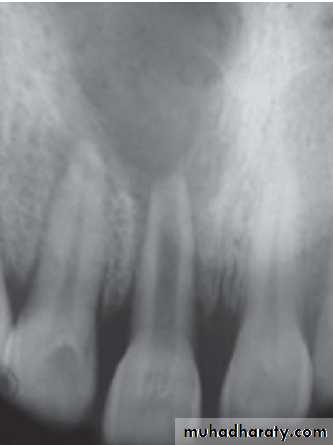

Radiographic Features

• Mostly discovered on routine radiographic examination• The earliest change in the periodontal ligament is found to be thickening of ligament at the root apex

• Lesion may be well circumscribed or poorly defined

• Size may vary from small lesion to large radiolucency exceeding more than 2 cm in diameter.

• Some amount of root resorption has been reported.